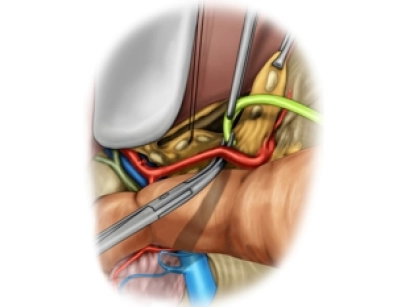

Supraaortische Eingriffe

Alloplastischer carotido-subclavialer Bypass bei A. subclavia-Stenose links